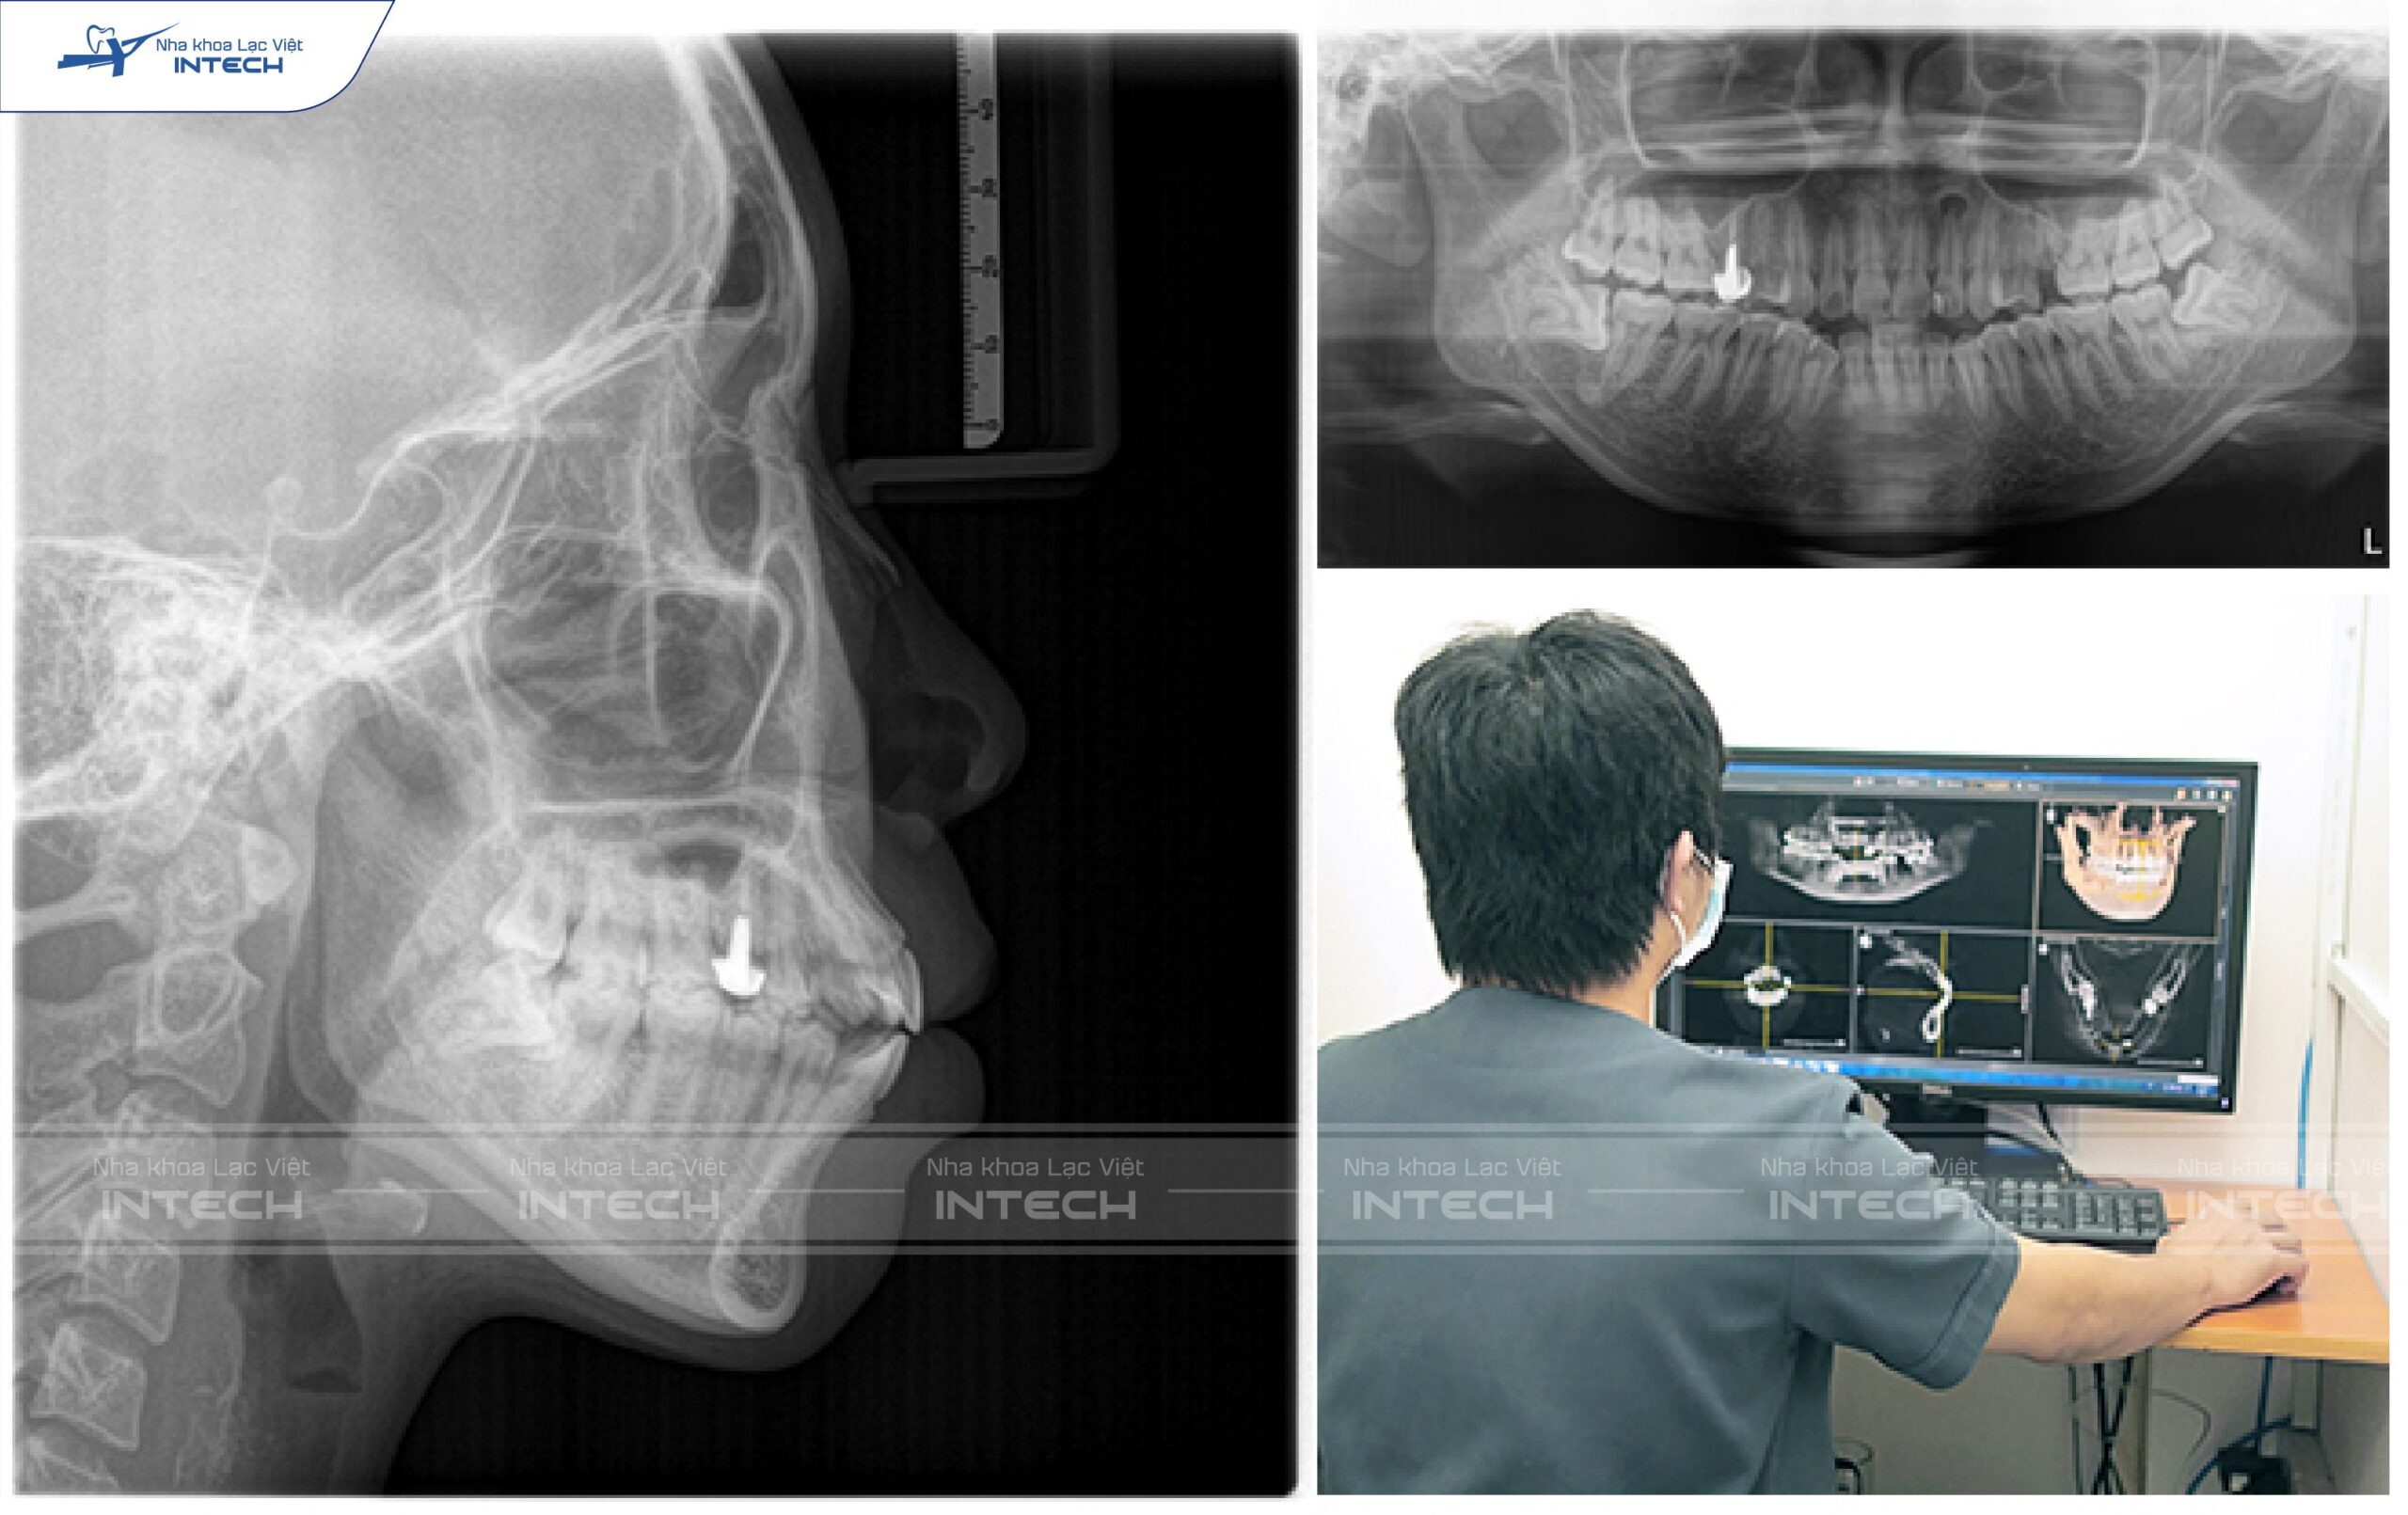

Để xác định được xương hàm của bạn có đủ thể tích cho mục tiêu điều trị hay không, bác sĩ cần chụp phim X quang để đánh giá. Phim thường được sử dụng là phim đo sọ nghiêng Cephalometric hoặc phim cắt lớp vi tính chùm tia hình nón CTCB.